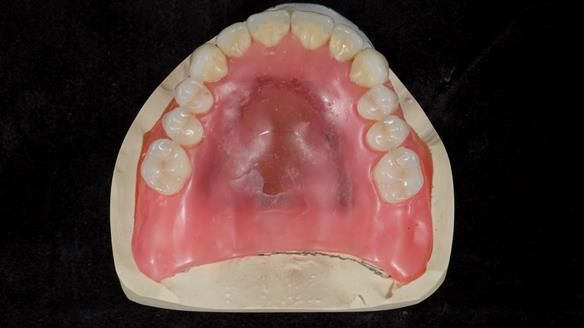

We provided her with an immediate upper denture (Mk 1), followed by a definitive metal-based upper denture (Mk 2). A lower removable partial denture was discussed, to be made only if needed once the upper treatment was complete. However, at review, this wasn’t necessary — Adnana had excellent neuromuscular control and function, even with a shortened dental arch (SDA).

Rowan, Sam Hesketh and Chris Hesketh provided the stunning technical work. I am very lucky to have them.

- Definitive denture (Mk 2), metal-based and custom-designed for her face